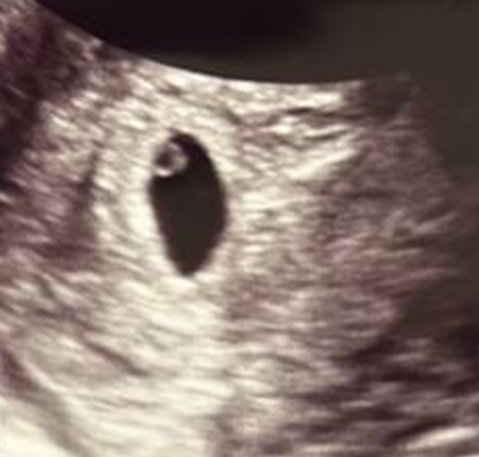

でも何が不安なのかって、1回目の妊娠の時は5週2日で胎嚢は8mm・丸いリングも結構しっかり見えていました。

こちらが当時のエコー写真です。

ただ、流産してしまったときのエコー写真なので、これが正解だったわけでもないのですが、、、

判断が難しい。